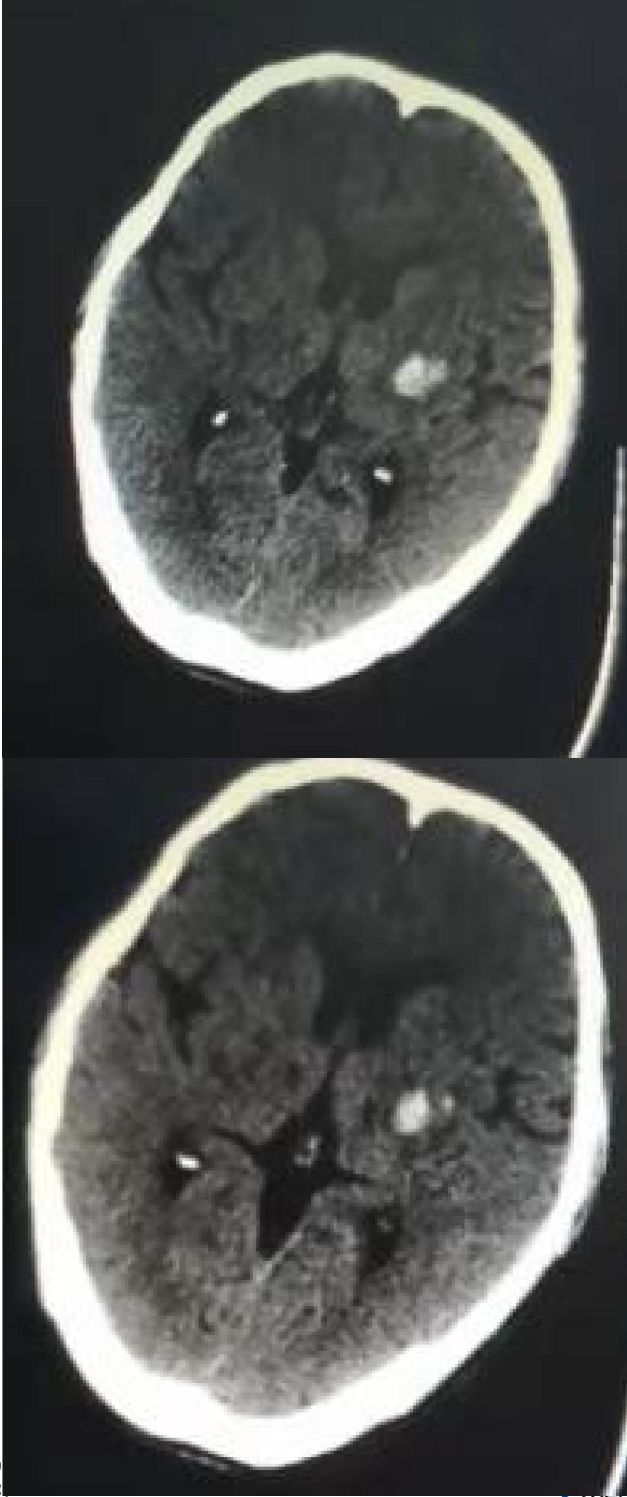

63岁男性,右侧肢体无力3小时入住某医院,因肢体无力加重转入。既往有高血压病、脑干出血病史。外院头影像学检查如下:

影像学可见:双侧侧脑室旁散在片状、卵圆形长T1长T2信号,其中左侧半卵圆中心病灶等T1,长T2信号,DWI呈高低不等混杂信号,结合病史,考虑为此次责任病灶。MRA并未见明显畸形或狭窄。

后补充CT:

诊断: 脑出血。

病例讨论:

该病例再次印证了CT是急性卒中的首要检查。因为MRI出血判读过于复杂,甚至可能模拟梗死,给治疗带来挑战。